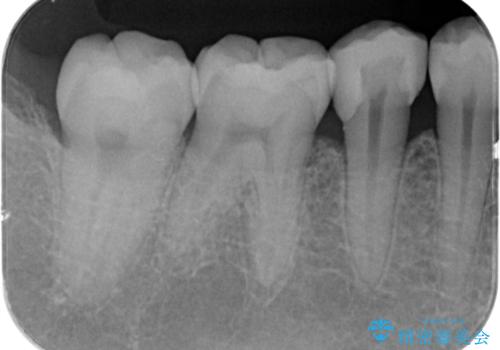

歯と歯の間の虫歯 セラミックインレーでの修復処置

- 検査の結果、歯と歯の間に虫歯が確認された患者様です。

虫歯を除去した後、セラミックインレーで修復処置を行います。

- 右下5 セラミックインレー 77,000円費用は治療当時の料金となります

レントゲン画像では写りにくい小さな虫歯も発見したため、そこも含めた形での修復処置を行いました。